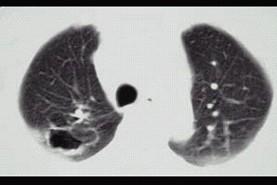

问题 21岁,近2个月来咳嗽,痰中带血丝,午后手心足底发热,盗汗、心悸,胸部CT见图,最可能的诊断是 ( )

选项 A、右上肺炎 B、肺囊肿 C、继发性肺结核空洞形成 D、右肺脓肿 E、右上肺癌性空洞形成

答案 C